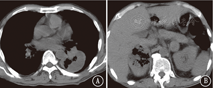

患者男,57岁,于2018年5月2日因"双侧颈部无痛性肿大淋巴结4个月"收入我院。既往吸烟史:吸烟30年,每天60支。入院查体:功能状态评分3分,双侧颈部触及多个肿大淋巴结,部分融合成团,最大直径约5 cm,质地硬,有压痛。左下肺呼吸音低,右侧腹部压痛,深触诊可触及肿物,大小6 cm×5 cm。左侧臀部可触及直径5 cm肿物。血常规:白细胞9.8×109/L,血红蛋白72 g/L,血小板677×109/L。肿瘤标志物:神经元特异性烯醇化酶21.91 ng/ml。肝肾功能及大、小便常规正常。骨髓穿刺活检:细胞形态未见异常,未见癌细胞;粒细胞、红细胞、巨核细胞增生活跃。颈部CT:鼻咽部未见异常,双侧颈部多发大小不等结节,考虑转移淋巴结。胸部CT:左肺下叶圆形软组织占位,边缘较光滑,未见分叶及毛刺,肿瘤大小63 mm×53 mm,内见坏死,增强扫描不均匀强化。纵隔肿大淋巴结,考虑转移。腹部CT:腹腔、双肾上腺肿物。右侧肾上腺明显,大小75 mm×53 mm,左侧肾下极与腰大肌分界不清,见图1。左侧臀部肿物,大小40 mm×51 mm,环周强化。颅脑磁共振成像、全身骨扫描未见异常。于2018年5月14日行左侧臀部切除活检:恶性肿瘤并坏死,免疫组织化学染色示:CKpan(+)、Vimentin(+)、CD3(-)、CD20(-)、CK7(-)、CK20(-)、Villin(-)、CK5/6(-)、P63(-)、NapsinA(-)、甲状腺转录因子-1(-)、Melan-A(-)、Melanoma(-)、CD30(-)、S100(-)、CD31(-)、Fli-1(-),不支持淋巴瘤、恶性黑色素瘤、血管源性肿瘤,不排除肉瘤样癌。2018年5月23日北京大学肿瘤医院会诊意见:支持肉瘤样癌。临床诊断:左肺肉瘤样癌伴颈部、纵隔、腹腔、盆腔淋巴结、双肾上腺、左臀部转移。输血治疗纠正贫血后于2018年6月5日开始口服安罗替尼抗肿瘤治疗(12 mg/d,第1~14天,21 d为1个周期)。2个周期后于2018年7月13日门诊复查颈部、胸、腹部CT:颈部、纵隔淋巴结较前略增大。左肺下叶肿块较前无明显变化,内见空洞。腹腔肿物较前略缩小,内见空洞。右侧肾上腺肿物较前略增大,内见空洞。左侧肾上腺肿物较前略增大,见图2。按照实体瘤疗效评价标准(RECIST)1.1版评价疗效为病情稳定。现继续安罗替尼靶向治疗中。

安罗替尼是我国自主研发的新一代抗肿瘤血管生成药物,已经被批准用于晚期NSCLC三线治疗。临床前研究显示,安罗替尼可以通过抑制血管内皮生长因子-A/血管内皮生长因子受体(VEGF-A/VEGFR)、成纤维细胞生长因子/成纤维细胞生长因子受体1(FGF/FGFR1)等多条信号途径抑制肿瘤血管生成,拮抗肿瘤生长和转移,并且比索拉非尼、舒尼替尼具有更强的抑制血管生成作用[12]。患者自2018年6月5日开始口服安罗替尼,2个周期后可见左肺及右肾上腺肿物内坏死、明显空洞形成,腹腔病灶略缩小并有小空洞形成,其余大部分病灶无明显增大,内部坏死较前不同程度增加。根据RECIST 1.1版评价为病情稳定。但根据Choi等[13]的标准,左肺及右肾上腺病灶评价部分缓解,颈部淋巴结、纵隔、腹腔淋巴结评价为病情稳定,总体评价为部分缓解。患者近期的临床获益能否转化为生存期获益,需要进一步观察。